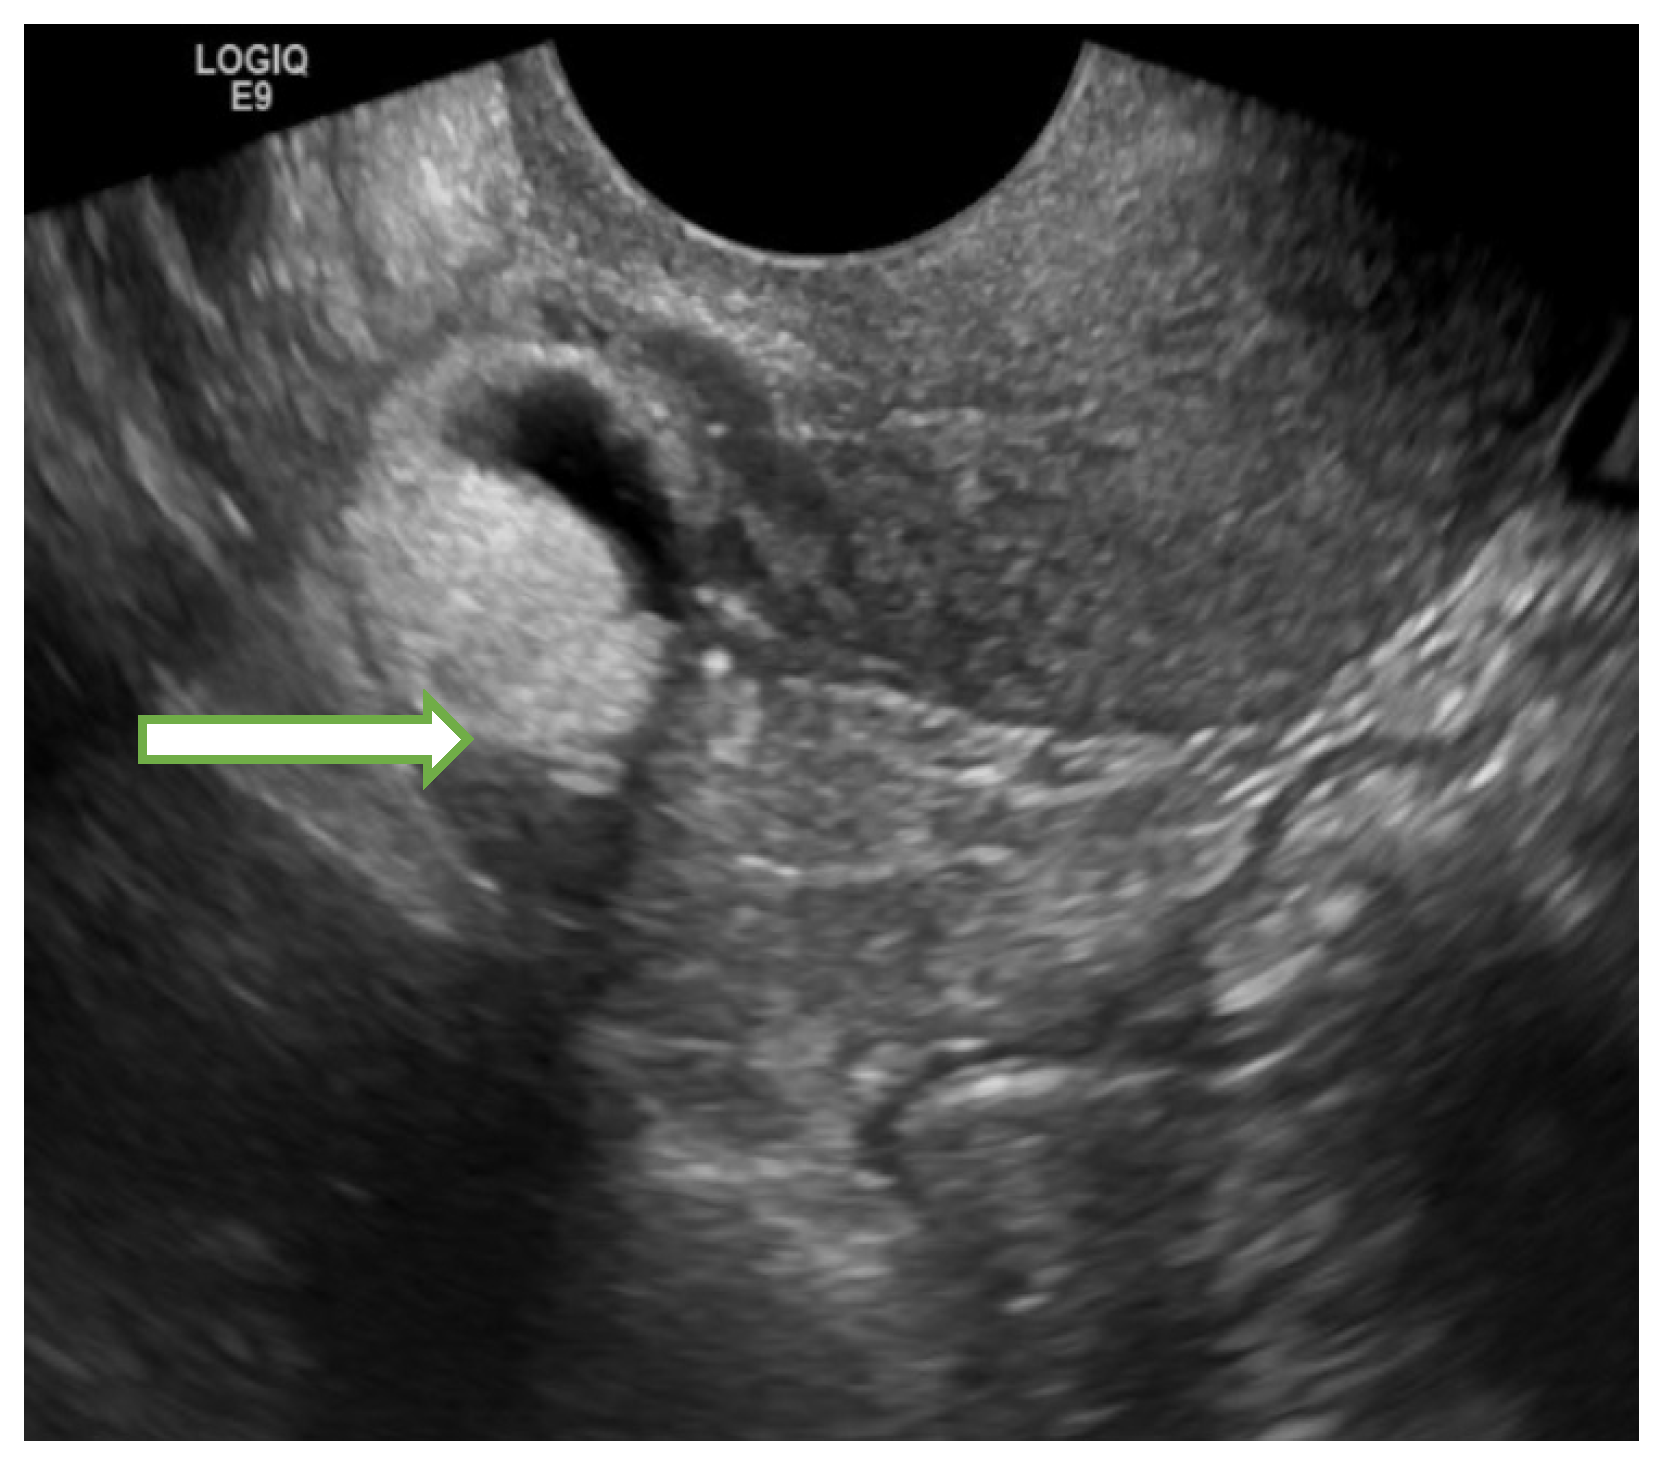

| Typical dermoid cyst <10 cm (Figure 2) | Follow up in 8–12 weeks | US specialist, gynecologist management or MRI | |||||

| Typical endometrioma <10 cm | Follow up in 8–12 weeks | US specialist, gynecologist management or MRI | |||||